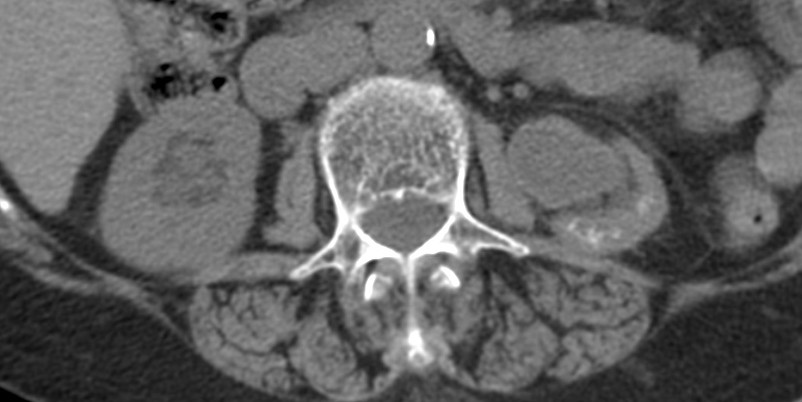

Se procede a realizar TC abdomino-pélvico con contraste en fase nefrográfica y excretora:

Conclusión: se nos presentó un caso de un paciente con una sospecha de infección renal complicada ya que tras cuatro días de tratamiento antibiótico no hubo mejoría. Ante los hallazgos observados en TC, podemos establecer el diagnóstico de pieloureteritis renal izquierda con signos de hidroureteronefrosis leve hasta vejiga.

4- Tomografía Computariazada:

No indicada sistemáticamente.

La TC es la técnica de elección para diagnosticar una pielonefritis ya que permite valorar la anatomía, la fisiología y los hallazgos patólogicos intra y extrarrenales. Soulen et al. confirmaron la validez de esperar 72 horas antes de realizar una prueba de TC en pacientes con sospecha de pielonefritis. En esta serie, el 95% de los pacientes con pielonefritis NO complicada presentaron resolución de la fiebre en 48 horas y el 100% en 72h.

Es de acuerdo universal que el TC pre y post contraste es la técnica de elección para valorar pielonefritis atípicas o complicadas, superando a la ecografía gracias a su gran capacidad de detectar anomalidades parenquimatosas.

- Protocolo: TC abominopélvico sin y con contraste en fase nefrográfica (70 seg) +/- fase tardía ( a los 7 – 10 min) solo si se sospecha obstrucción.

- TC sin contraste permite valorar la presencia de gas, cálculos, hemorragias, aumento del tamaño del riñón, masas inflamatorias y obstrucciones.

- TC con contraste: Las áreas afectadas del parénquima aparecen como zonas con baja atenuación debido al edema. Las áreas hiperdensas son menos frecuentes y corresponden a focos de hemorragia. Estos hallazgos son mejor valorables a través de la aplicación de contraste, ya que un TC en vacío pueden pasar desaprecibidas.